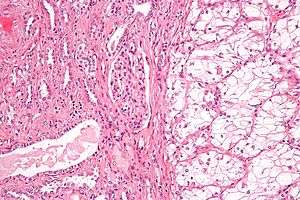

| Micrograph of the most common type of renal cell carcinoma (clear cell)—on right of the image; non-tumour kidney is on the left of the image. Nephrectomy specimen. H&E stain | |

Histopathology

The gross and microscopic appearance of renal cell carcinomas is highly variable. The renal cell carcinoma may present reddened areas where blood vessels have bled, and cysts containing watery fluids.[54] The body of the tumour shows large blood vessels that have walls composed of cancerous cells. Gross examination often shows a yellowish, multilobulated tumor in the renal cortex, which frequently contains zones of necrosis, haemorrhage and scarring. In a microscopic context, there are four major histologic subtypes of renal cell cancer: clear cell (conventional RCC, 75%), papillary (15%), chromophobic (5%), and collecting duct (2%). Sarcomatoid changes (morphology and patterns of IHC that mimic sarcoma, spindle cells) can be observed within any RCC subtype and are associated with more aggressive clinical course and worse prognosis. Under light microscopy, these tumour cells can exhibit papillae, tubules or nests, and are quite large, atypical, and polygonal.

The recommended histologic grading schema for RCC is the Fuhrman system (1982), which is an assessment based on the microscopic morphology of a neoplasm with haematoxylin and eosin (H&E staining). This system categorises renal cell carcinoma with grades 1, 2, 3, 4 based on nuclear characteristics. The details of the Fuhrman grading system for RCC are shown below:[58]

Nuclear grade is believed to be one of the most imperative prognostic factors in patients with renal cell carcinoma.[22] However, a study by Delahunt et al. (2007) has shown that the Fuhrman grading is ideal for clear cell carcinoma but may not be appropriate for chromophobe renal cell carcinomas and that the staging of cancer (accomplished by CT scan) is a more favourable predictor of the prognosis of this disease.[59] In relation to renal cancer staging, the Heidelberg classification system of renal tumours was introduced in 1976 as a means of more completely correlating the histopathological features with the identified genetic defects.[60]